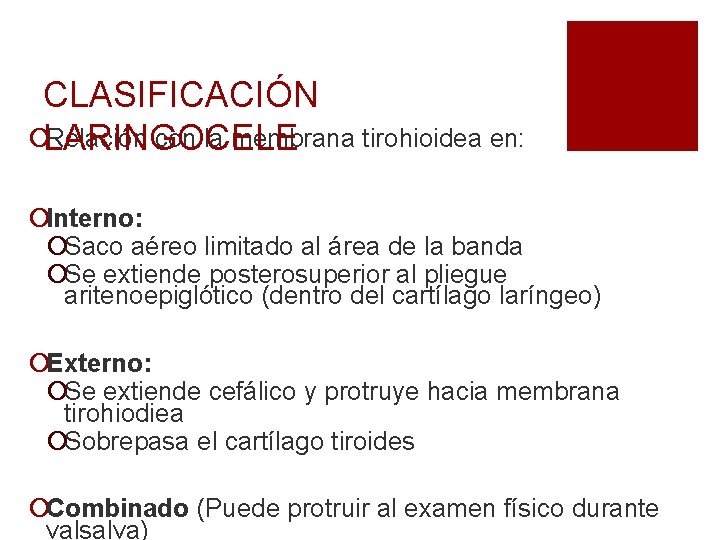

CLASIFICACIÓN ¡LARINGOCELE Relación con la membrana tirohioidea en: ¡Interno: ¡Saco aéreo limitado al área de la banda ¡Se extiende posterosuperior al pliegue aritenoepiglótico (dentro del cartílago laríngeo) ¡Externo: ¡Se extiende cefálico y protruye hacia membrana tirohiodiea ¡Sobrepasa el cartílago tiroides ¡Combinado (Puede protruir al examen físico durante valsalva)